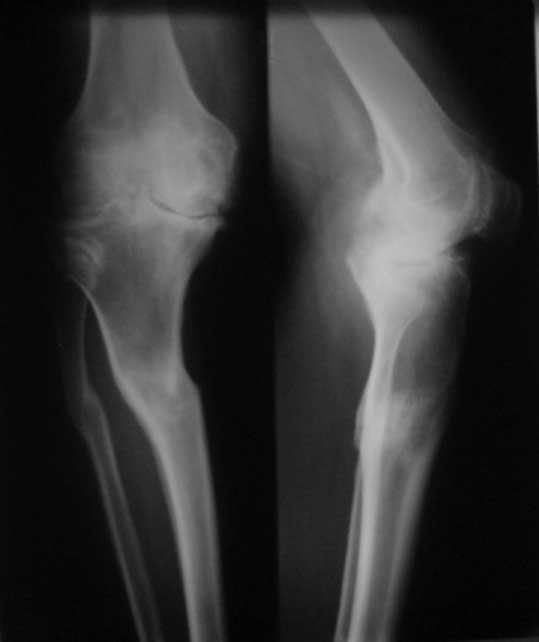

У пациента 50 лет имеется разгибательная контрактура через 8 меспосле ТКА. Уважаемые коллеги. Пациент 8 мес после операции ТКА, в анамнезе – неправильно сросшийся перелом голени, коррекция оси (снимки прилагаются. В настоящее время имеется разгибательная контрактура 10/5/0, на операционном столе было 90/0/5, на момент выписки движения 50/0/0 в надежде на дальнейшую разработку. До эндопротезирования 40/10/0. Глубокая инфекция исключена. Ротация бедренного компонента в норме (по КТ). Вопросы: насколько для такого ограничения критична некорректная установка б/б компонента (я намерял 7 град)? Причина нынешнего состояния, артрофиброз? Какие действия следует предпринять, удаление рубцов, релиз головок 4-главой мышцы? Что-либо другое, ваше мнение? С уважением, Максим Агалаков, Екатеринбург.